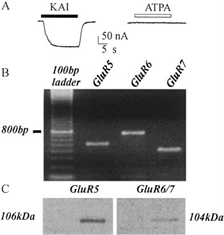

Leggi di Più..Espressione dei Recettori Neurotrasmettitoriali Umani del Lobo Temporale Epilettico in Oociti di Xenopus: un Approccio Innovativo per lo Studio dell’Epilessia

Lo studio introduce un modello innovativo per lo studio dell’epilessia,...

Leggi di Più..Pubblicazioni & Ricerche